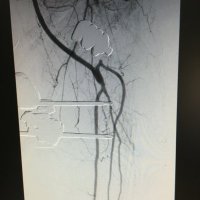

Jefe de Servicio de Angiología y Cirugia Vascular. Hospital Universitario Virgen de las Nieves, Granada

Trends in treatment strategies and perioperative outcomes for complex abdominal aortic aneurysms: a VASCUNET report” 🚨NEW PAPER ACCEPTED IN EJVES ✅international collaboration ✅first-time data from Portugal. ✅complex AAA treatment strategies👏🏻. High-impact work !